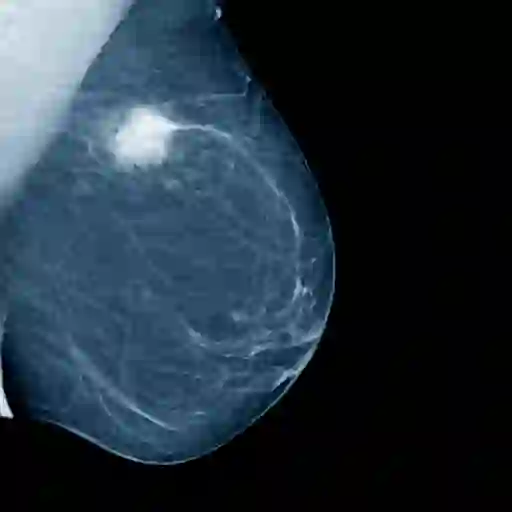

事实:乳房x光检查不能“传播”乳腺癌

乳房x光检查可能会不舒服,因为乳房被压平以提供最佳质量的图像。但是乳房x光检查不能引起或者传播癌症。“我希望我能告诉有乳房的人一件事:如果你超过30岁,现在就做基线乳房x光检查,”来自佐治亚州亚特兰大的38岁的玛丽莎·科科伦(Marisa Corcoran)说,她在2022年6月被诊断出患有0-1期乳腺癌。“我的妇科医生让我第一次做乳房x光检查的原因完全不同。如果我等到“正常”年龄才做第一次乳房x光检查,我就不会得到早期诊断。(注:对于第一次乳房x光检查的年龄,不同机构的官方建议有所不同;和你的医生谈谈什么适合你。)

事实:乳腺癌很难发现

46岁的梅根-克莱尔·蔡斯来自佐治亚州亚特兰大,由于家族癌症史,她在35岁时接受了预防性乳房x光检查。结果是阴性,她被告知五年后再做一次。当蔡斯开始出现不寻常的症状时,几位不同的专家都排除了乳腺癌的可能性,因为乳房x光片清晰,没有肿块或任何其他更常见的症状。她坚持了两年,直到乳房有感觉后,她才再次接受乳房x光检查,并被诊断为IIA期乳腺癌。